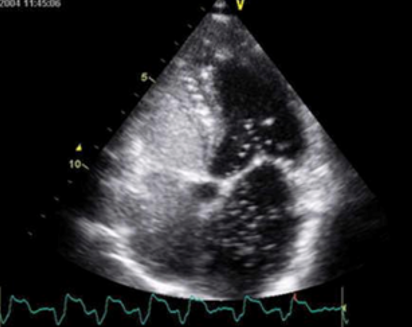

Рисунок 1 Эхокардиография при ОАП у собаки

Рисунок 2 Открытый артериальный проток